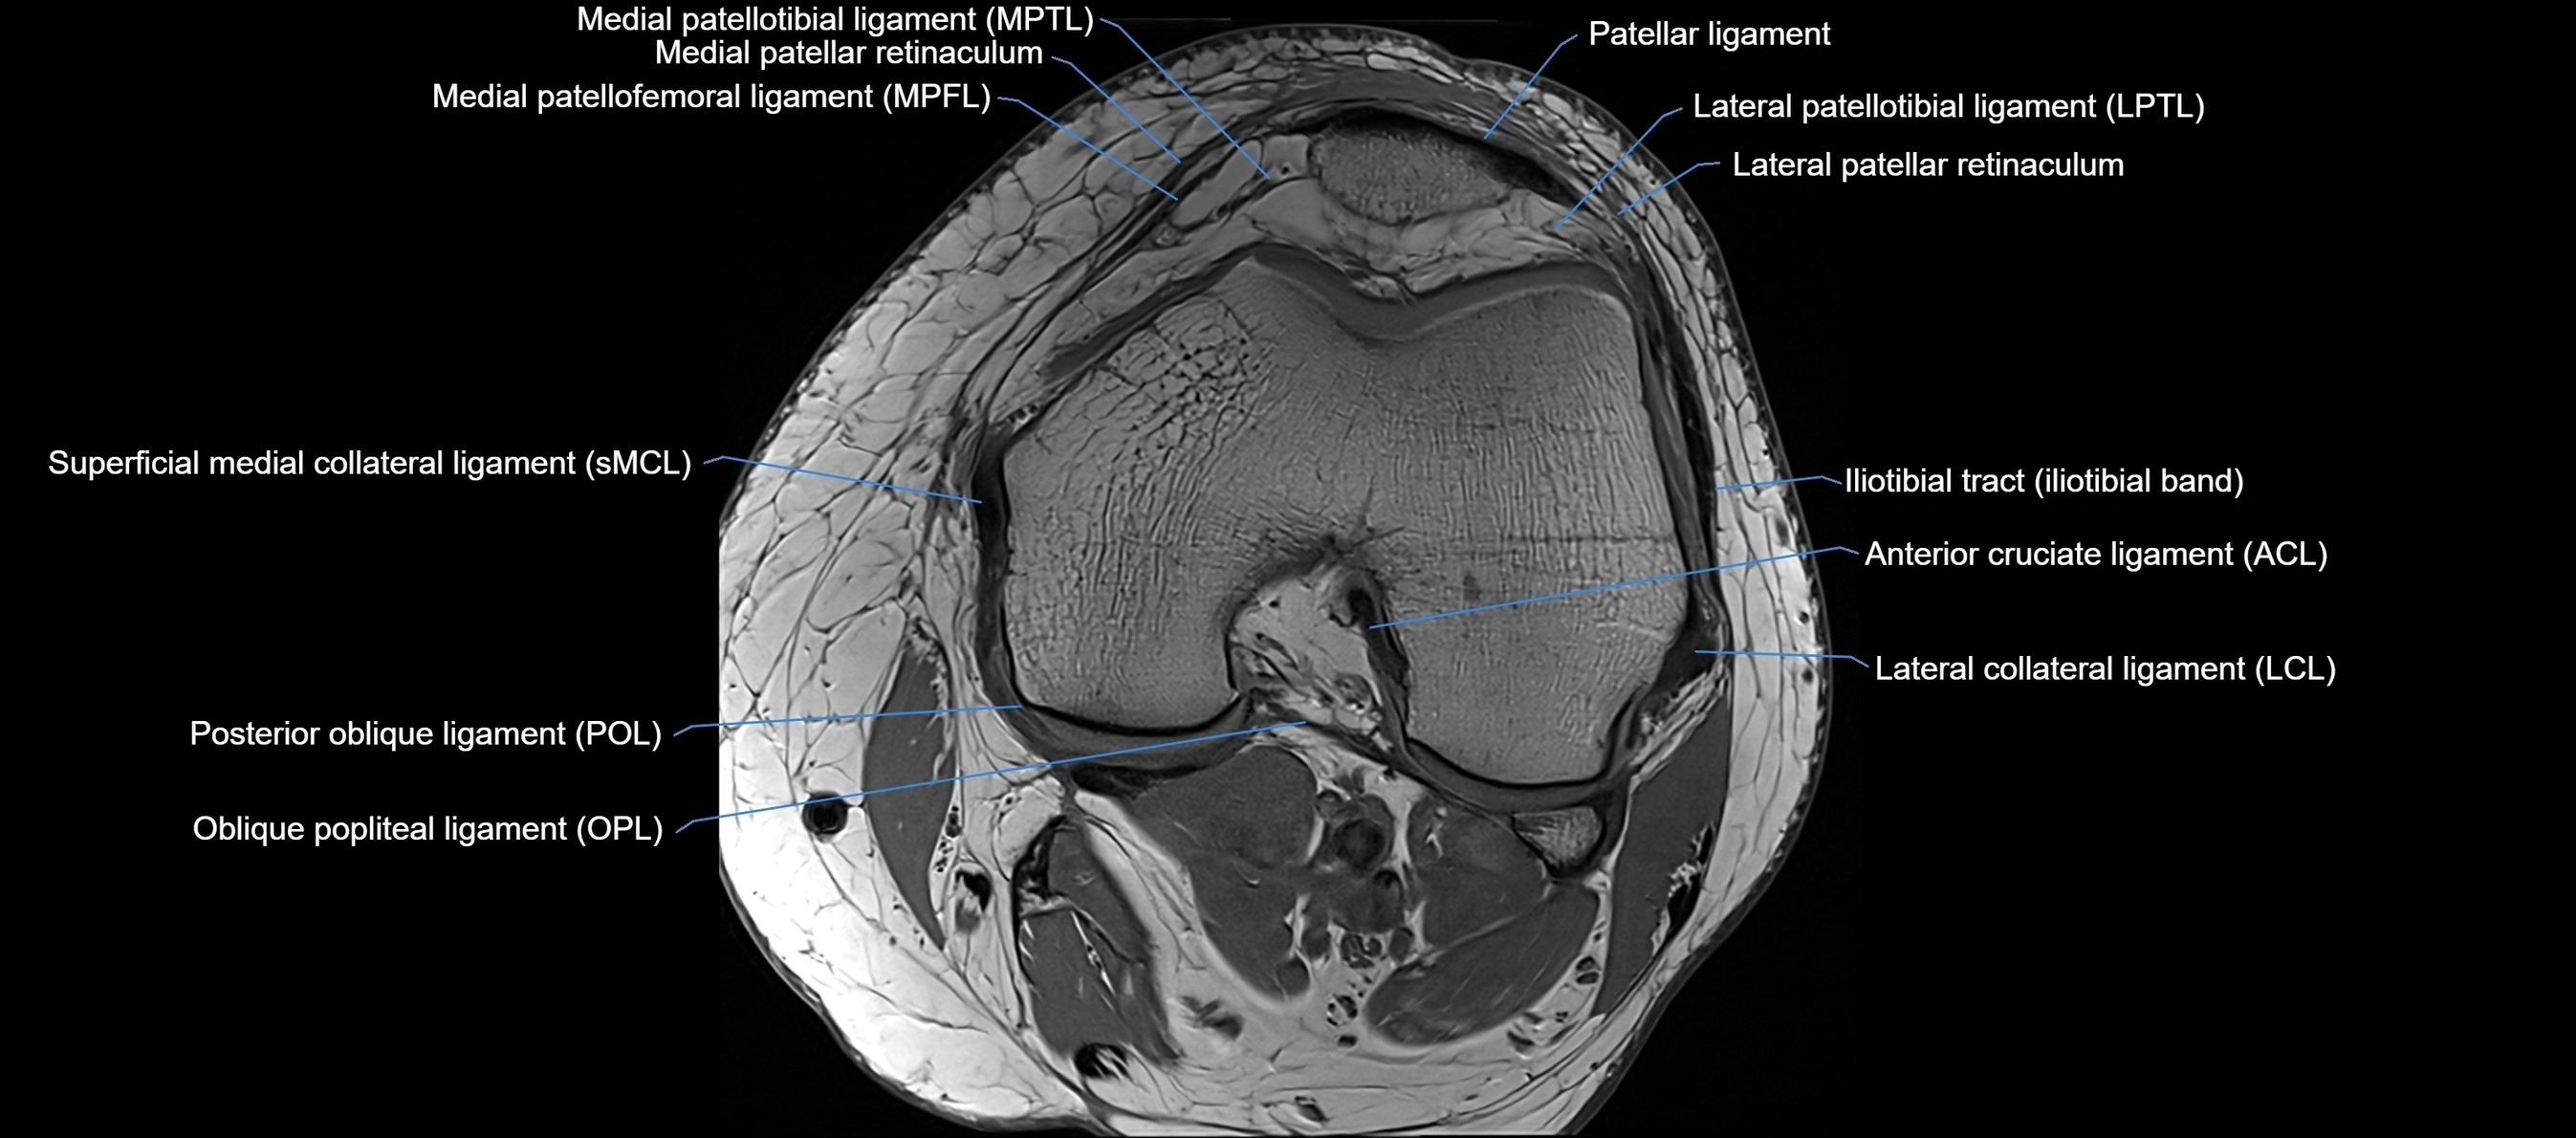

MRI images

image